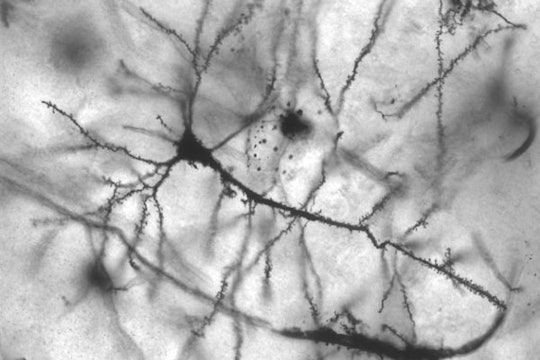

Image by MethoxyRoxy, reproduced under CC BY-SA 2.5

Neurons die with grace